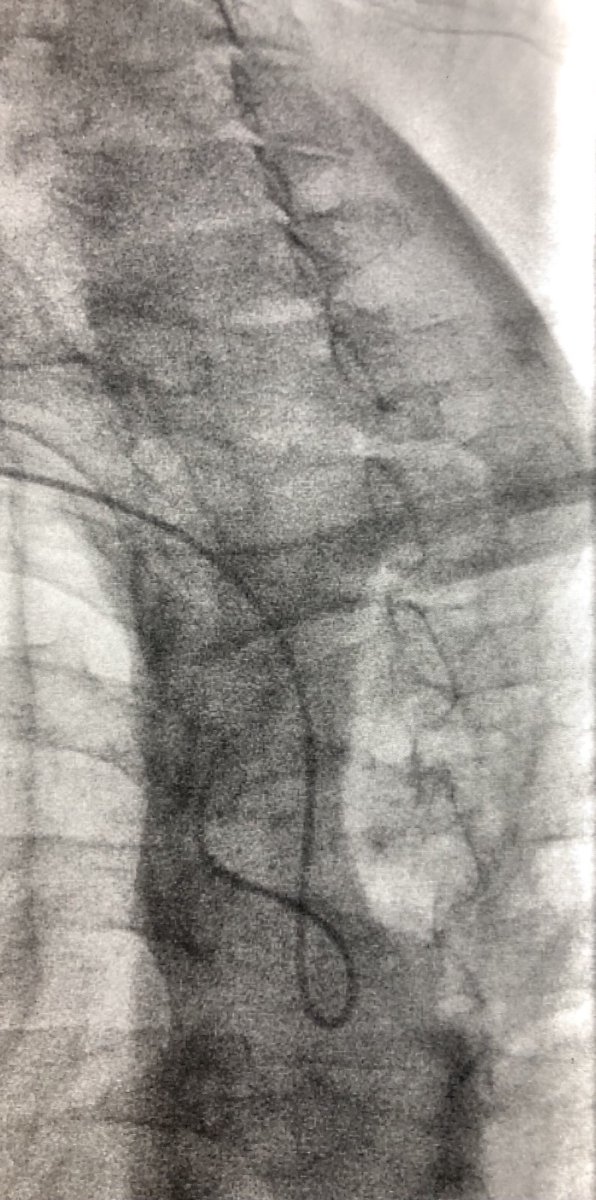

Late case before time off for the 4th! Open toe wound w/ osteo. Antegrade crossing of occluded peroneal. Tibial access to cross long segment ATA occlusion after failed antegrade attempt. Initial access too close to distal cap so moved distal #CLI #SCAIPAD #wifeissounderstanding